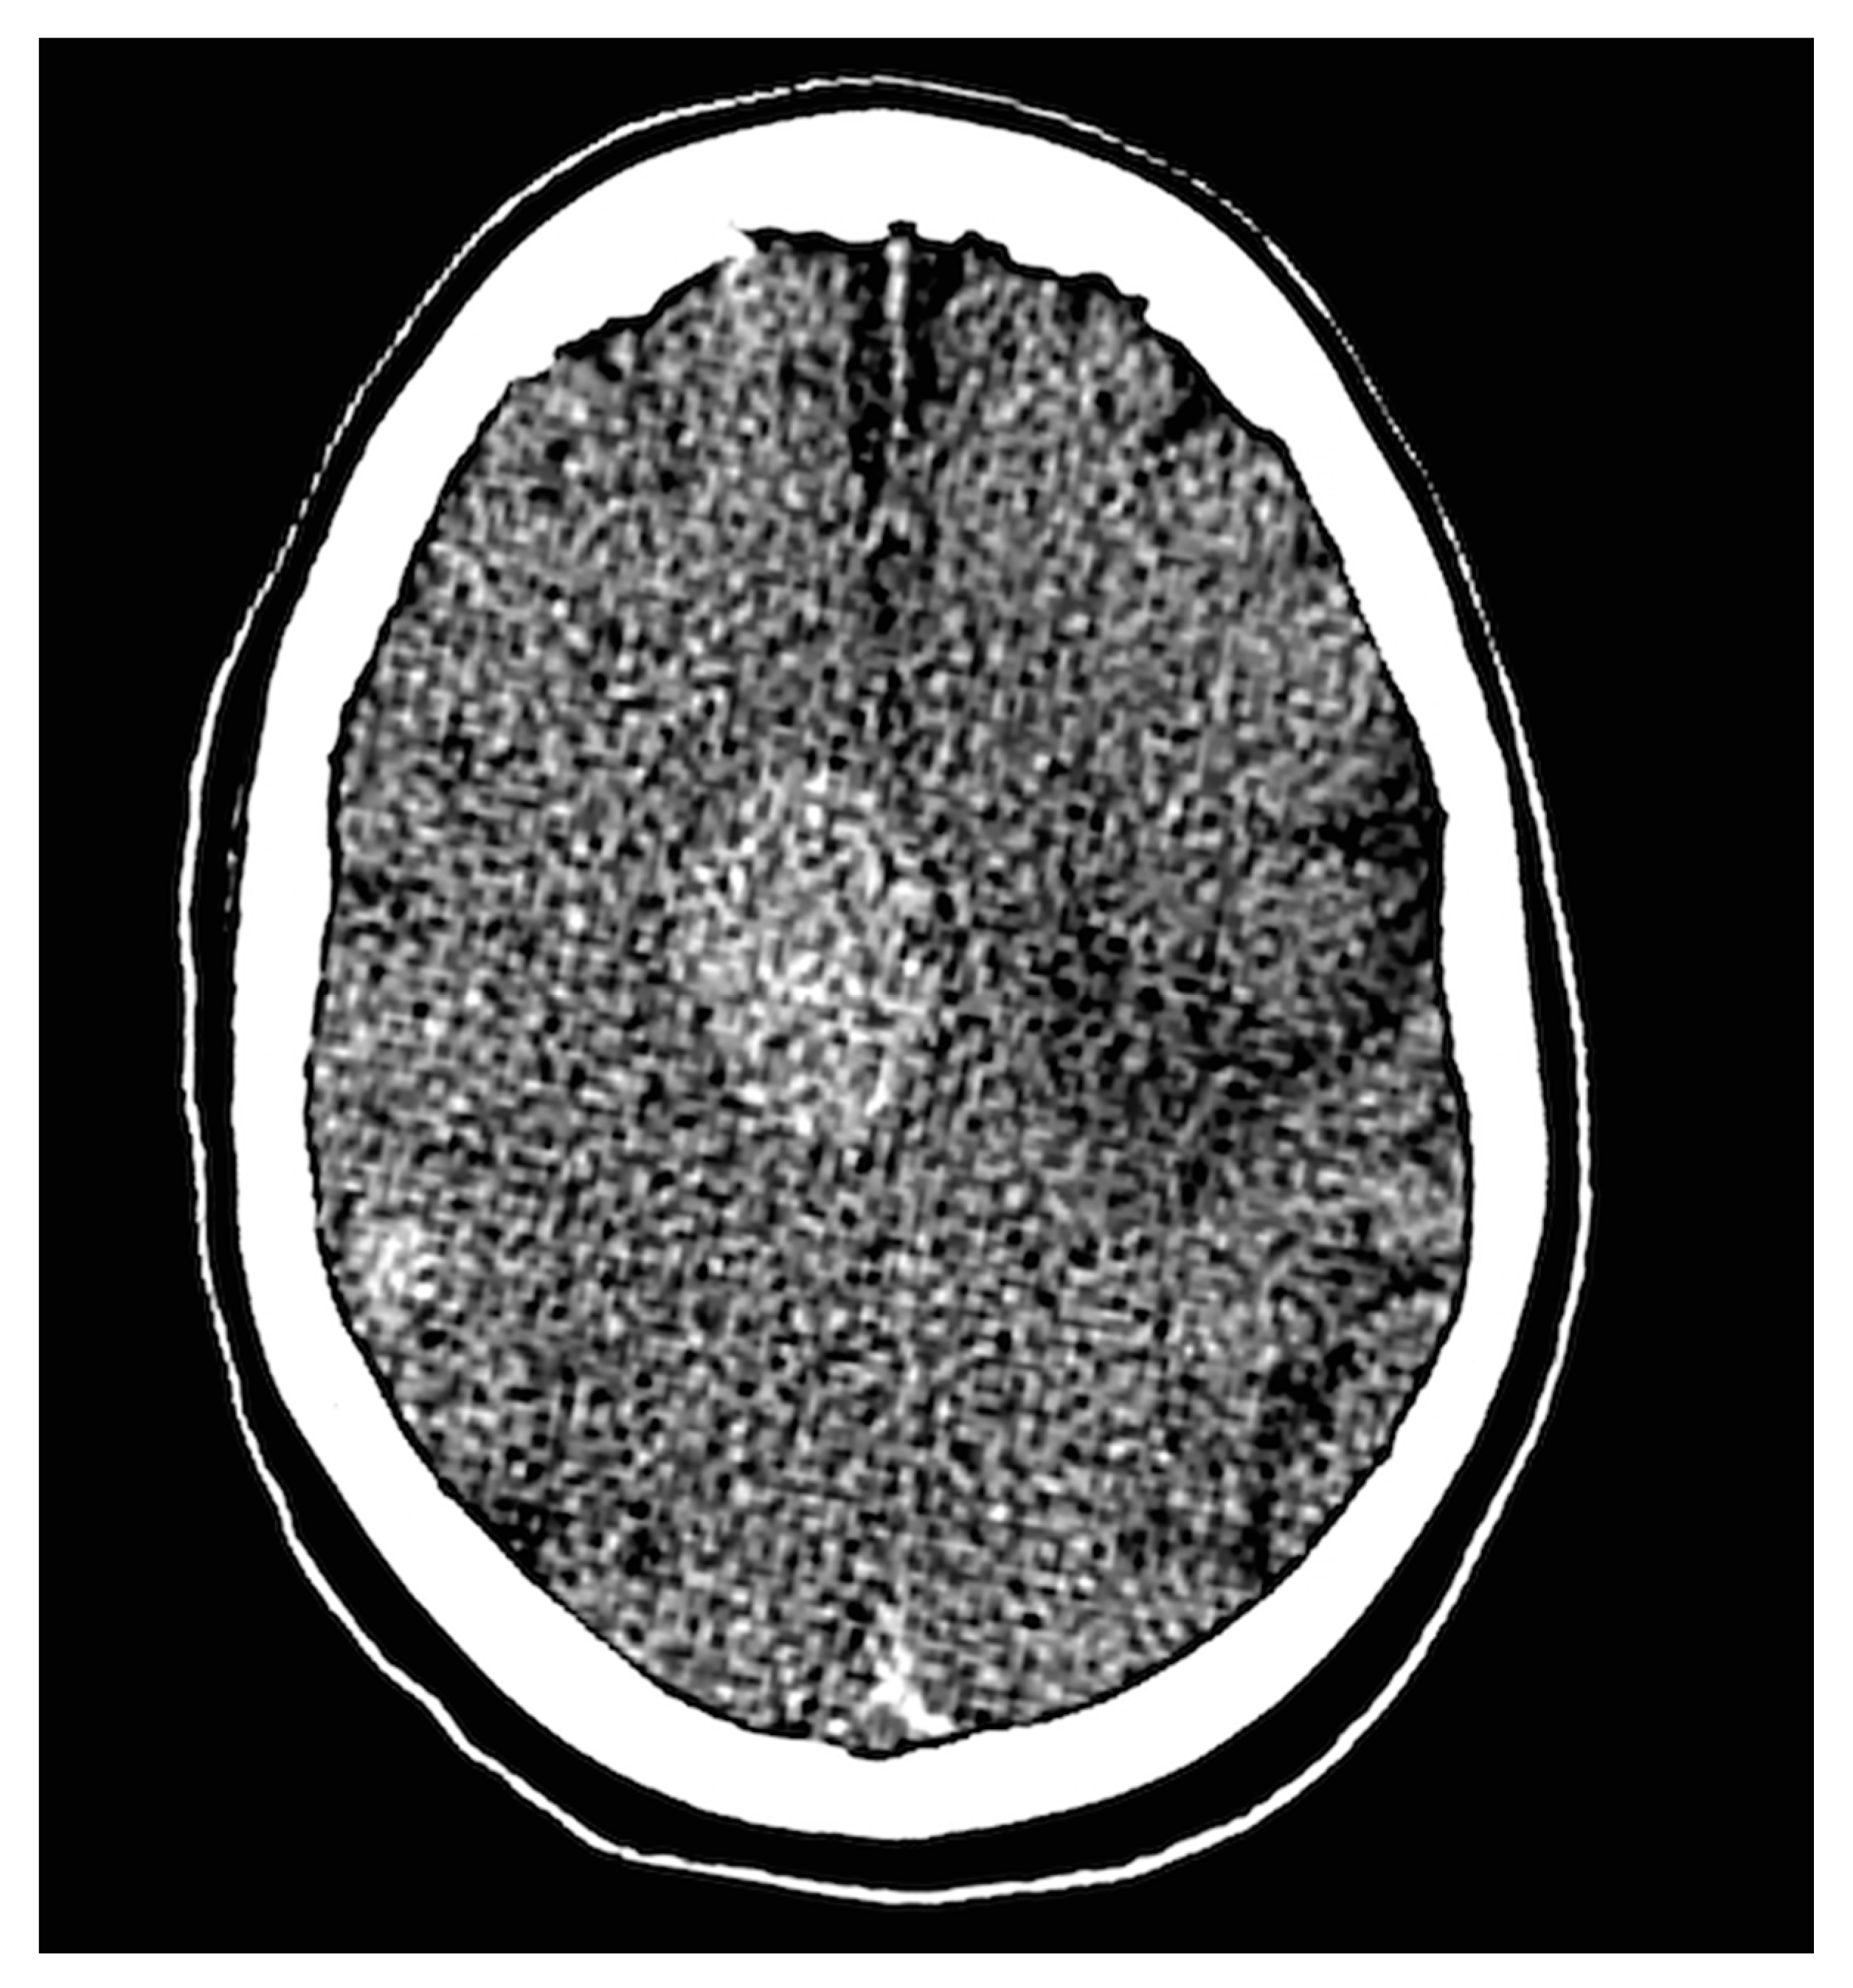

| PMCT findings in absence of brain autopsy | 3 | 3 | Cerebral mass, multiple cerebral metastases, and one case with post-procedural hypoxia. One of these cases is illustrated in Figure 3. |